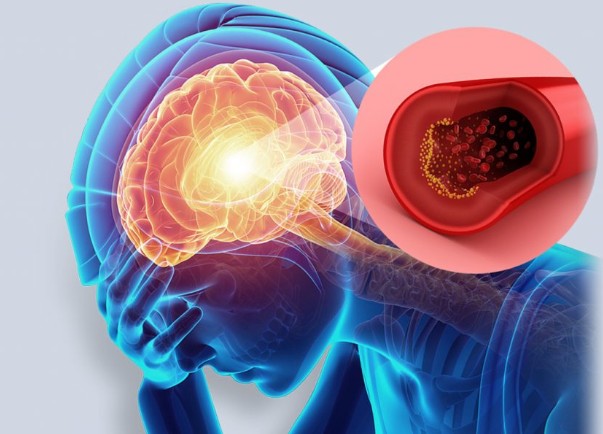

오늘은 많은 분들이 두려워하는 질환, 뇌경색의 초기 증상에 대해 이야기하려 합니다. 뇌경색은 뇌혈관이 막혀 뇌 조직이 손상되는 질환으로, 치료 시기를 놓치면 영구적인 장애를 남기거나 생명을 위협할 수 있습니다.

뇌경색 초기증상 증상이 갑작스럽게 나타나는 것이 특징이며, 응급 상황에 해당하므로 증상을 정확히 알고 신속하게 대처하는 것이 매우 중요합니다. 지금부터 뇌경색의 10가지 주요 초기 증상들을 꼼꼼히 살펴보고, 건강을 위한 첫걸음을 함께 시작해 볼까요? 🧠

뇌경색은 뇌의 어느 부위가 손상되었는지에 따라 증상이 다르게 나타납니다. 증상이 한쪽 신체에 집중되어 나타나는 것이 특징이며, 증상이 나타났다가 24시간 내에 사라지는 경우(일과성 허혈 발작)도 있지만, 이는 뇌경색의 전조 증상이므로 반드시 병원을 찾아야 합니다. 다음은 뇌경색 환자들이 흔히 겪는 10가지 주요 초기 증상입니다.

- 설명: 특별한 원인 없이 갑자기 머리가 깨질 듯한 심한 두통이 발생합니다. 이는 뇌혈관이 막히거나 출혈이 발생하면서 뇌압이 상승하기 때문입니다.